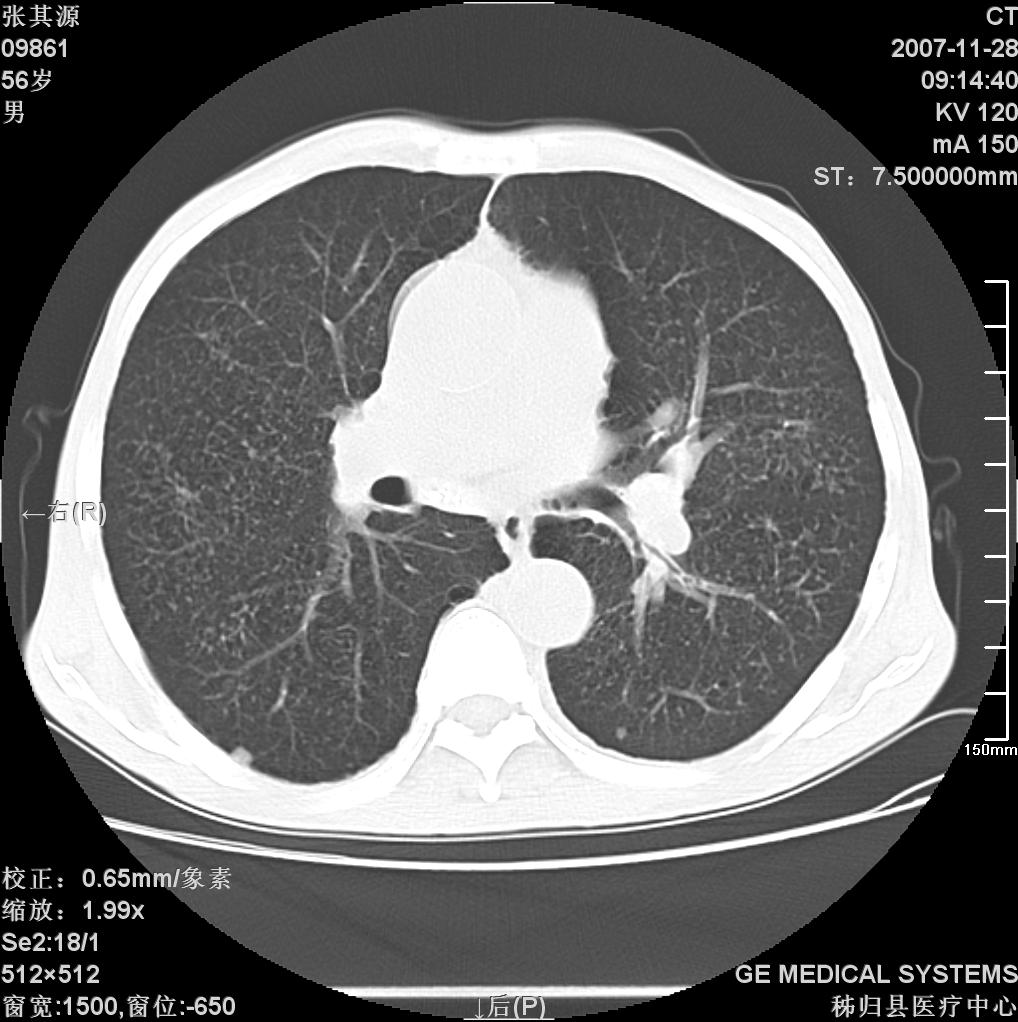

患者因阻塞性黄疸入院,发病前10天持续中等程度发烧.术前检查发现两肺弥漫性病变,请各位大虾会诊,除了考虑急性血源性肺结核外,还有其他什么疾病可能.

补充一下,该患者没有与尘肺相关职业史。请大家帮忙会诊一下,外科医生打算为其做胆总管肿瘤做手术的,现在在等我们的结果。谢谢各位了。

双肺多发粟粒样病灶,右肺胸膜下结节样病灶,气管前腔静脉后及隆突下均见肿大淋巴结,结合胆道肿瘤病史首先考虑转移。另外心影密度略低,时间格显示,是否有贫血?查明白再手术吧!